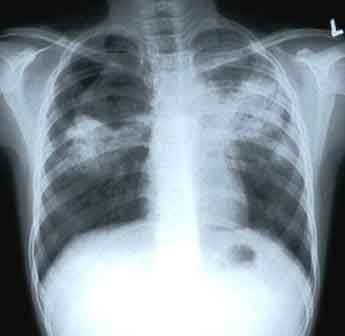

295 People Of Every 100 Thousand Pakistanis Are Sick With Tuberculosis Or Tb Disease